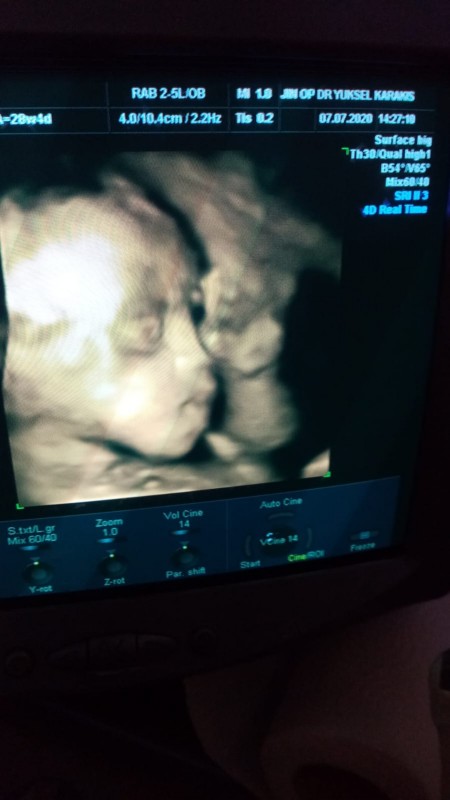

image

bizde bunu özelde ekrandan cektik kağıt olarakta aynisini aldik

8 Temmuz 2020 (258 puan) yorumladı

Kontrolde canım dr odasindaki ultrason bu 4 boyutlu

8 Temmuz 2020 (5 puan) yorumladı

Teşekkür ederim canım kaç haftalıktı acaba burda bebeginiz

Tam 7 aylıktı haftasını hatirlamiyorum canim